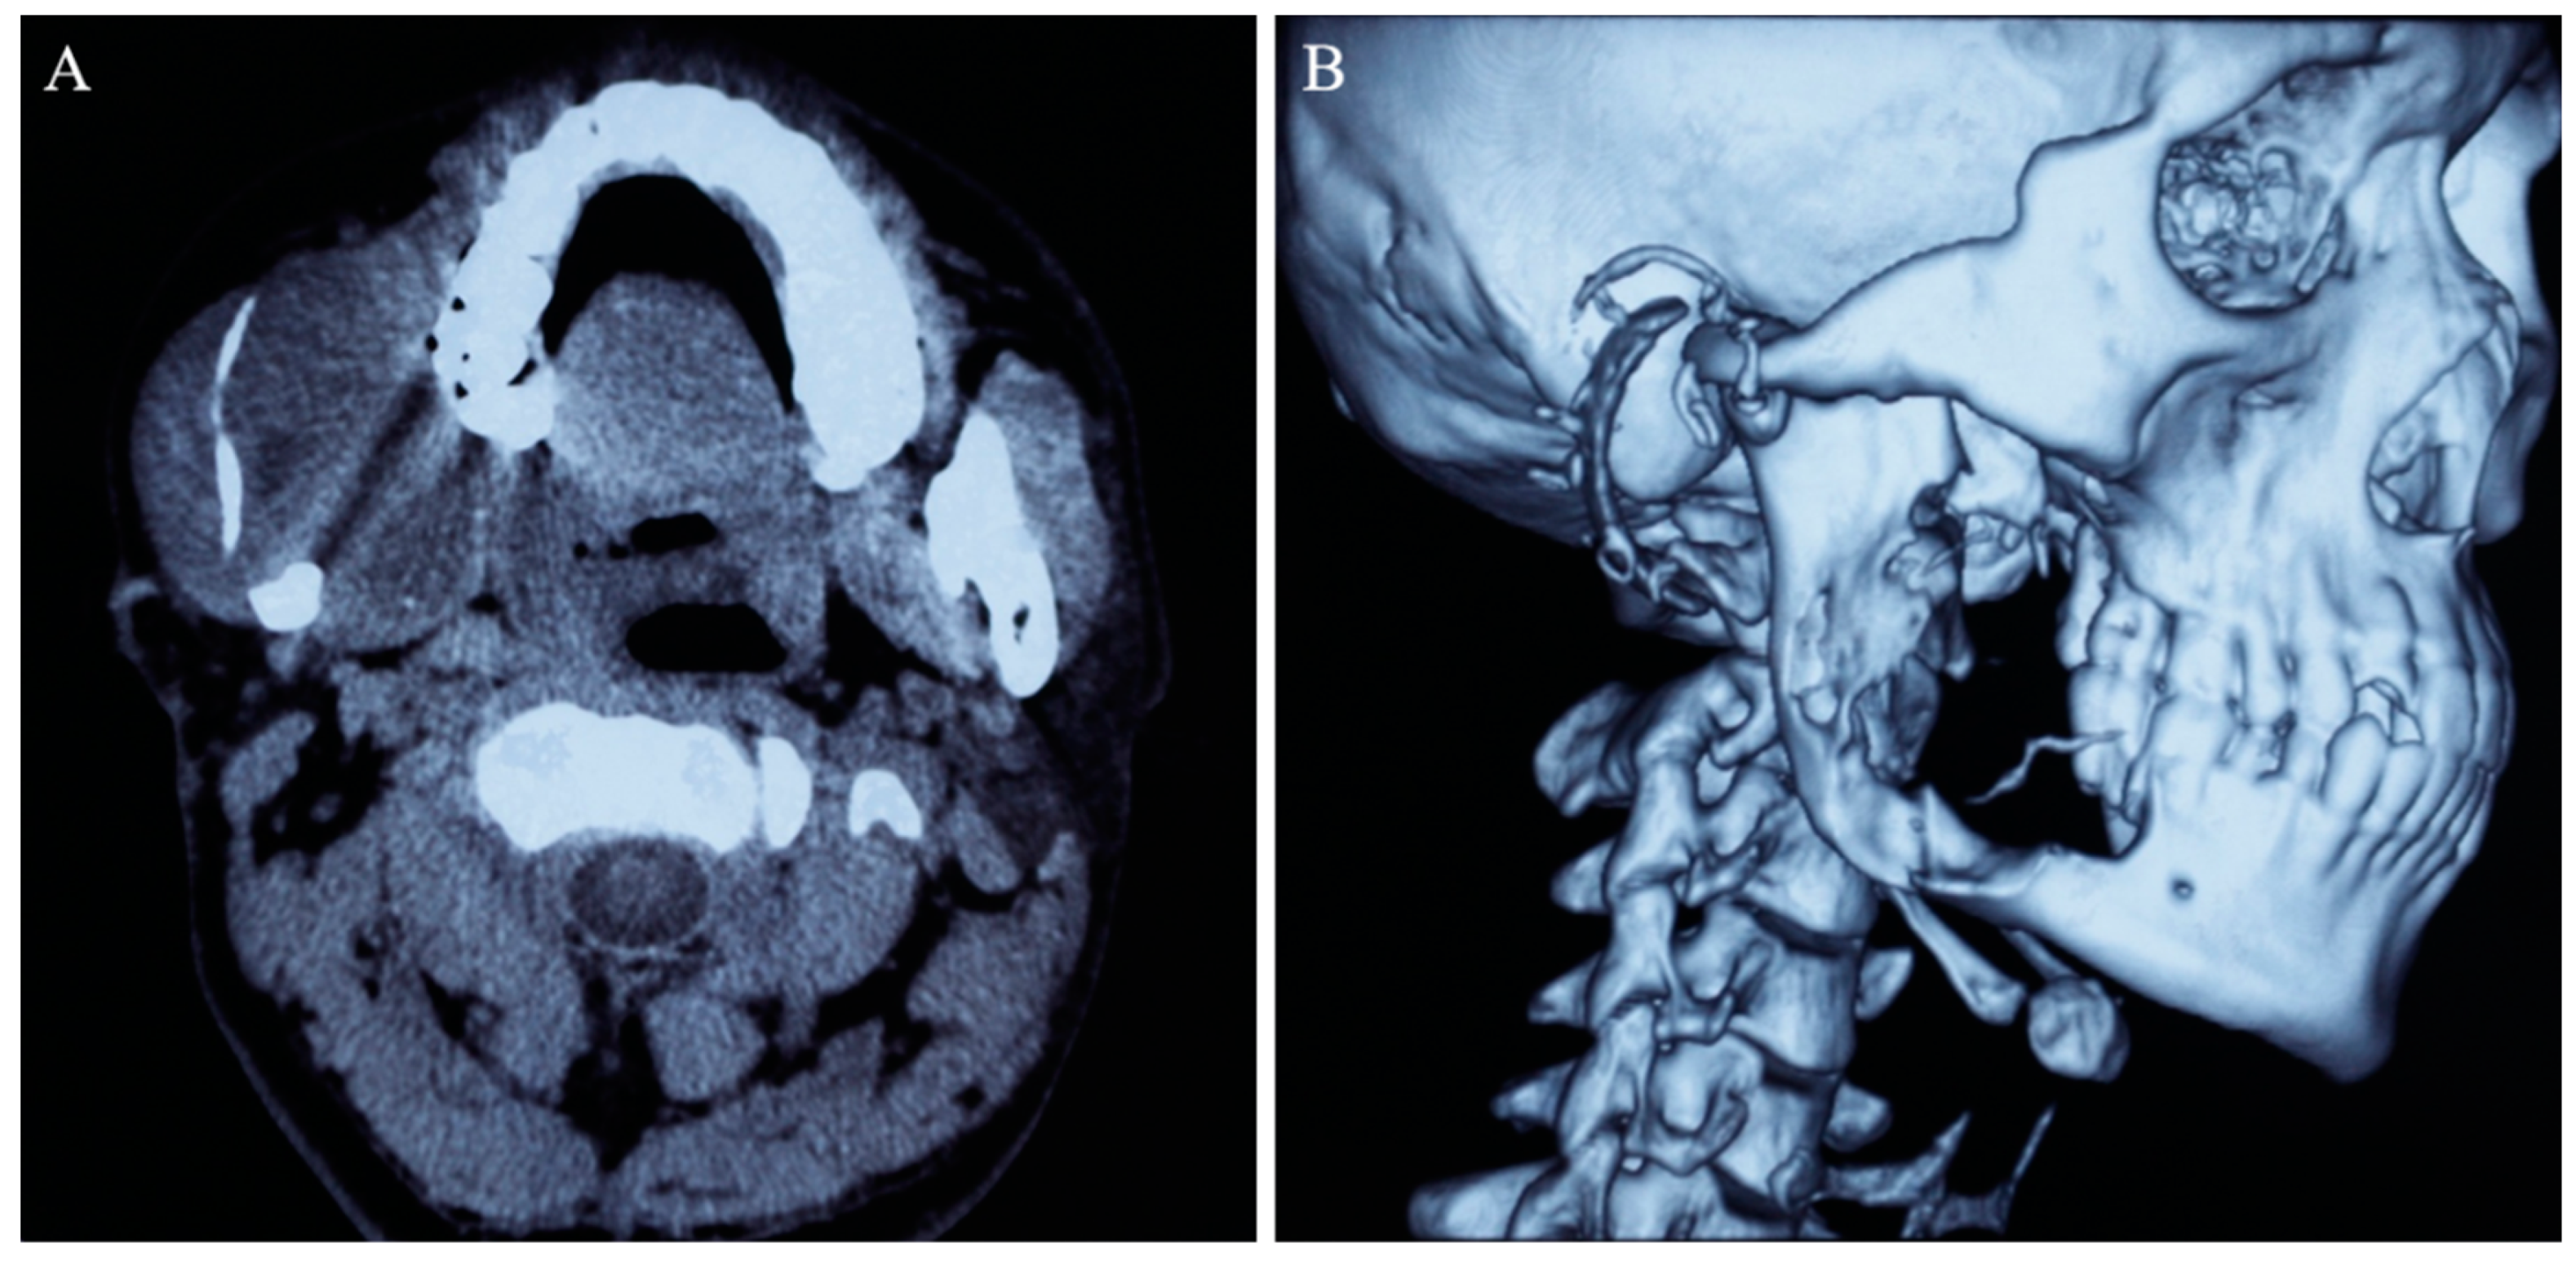

This patient had been previously diagnosed with ameloblastoma and received marsupialization at the age of 25. He then presented with the initial symptoms of loosening of the right lower wisdom tooth, swelling of the right cheek, and recurrent overflow of dark brown liquid oral discharge. The initial cone beam computed tomography (CBCT) examination revealed a huge unilocular radioluscent lesion in the right mandible, extending from the right mandibular body to the ascending ramus (Figure 1). Cortical-bone destruction in the buccal and lingual regions and knife-edge root resorption of the right lower second molar were observed. Such evidence strongly implicated the diagnosis of ameloblastoma, and eventually this diagnosis was validated by histopathological examination. The patient underwent marsupialization in a local hospital, and the blood examination showed no relevant abnormalities in hematology or biochemistry during hospitalization.

Figure 1.

CBCT imaging (A) and three-dimensional reconstruction of the skull (B) demonstrated extensive bony destruction and soft tissue involvement by the right mandibular tumor.